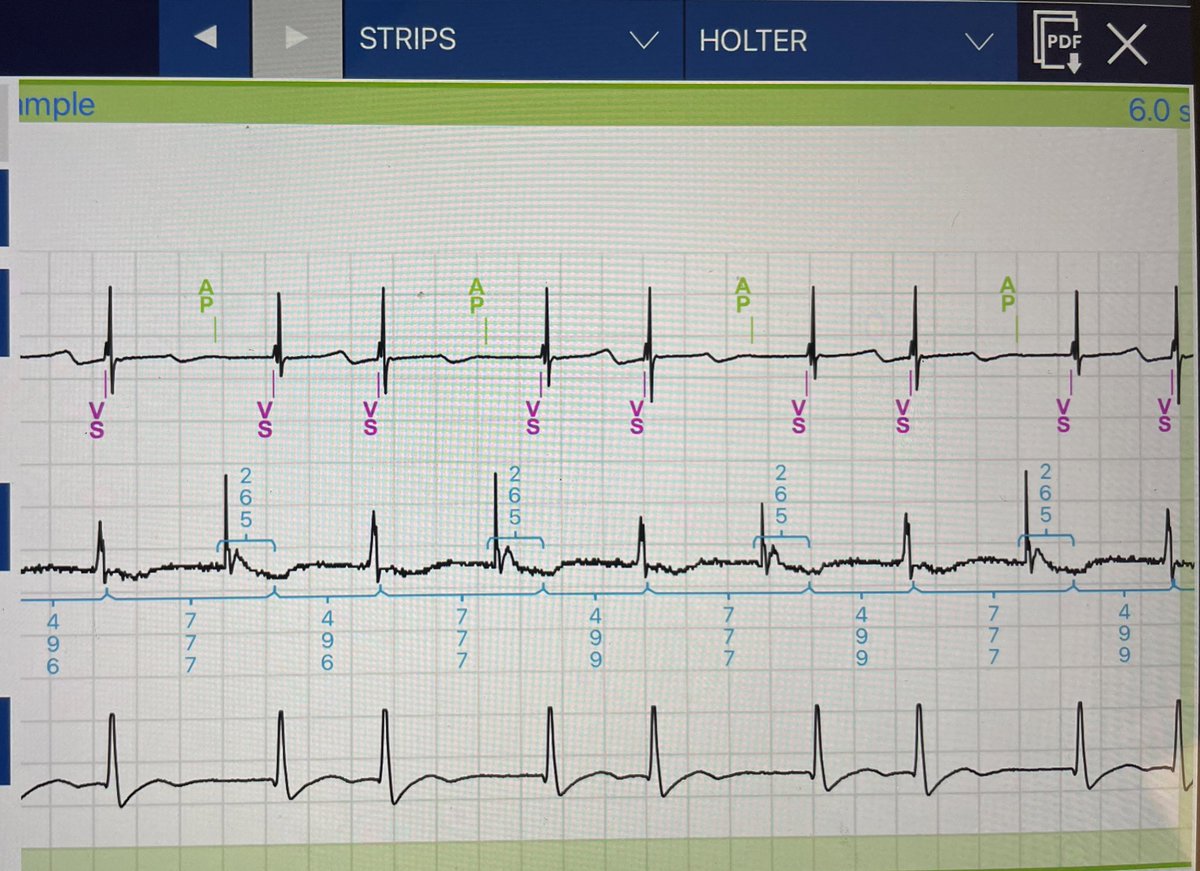

70 F with DCM, EF 35%, LBBB. Declined ICD. At implant, RV-LV 20ms was best, but left it adaptivCRT to test. Here are no pacing, adaptiv, RV-LV 20ms (still best) at 2 mo fu. How do you program your #LOT-CRT? @AjayPMD Roderick Tung Robert Schaller AFPanico Andreas Müssigbrodt #EPeeps